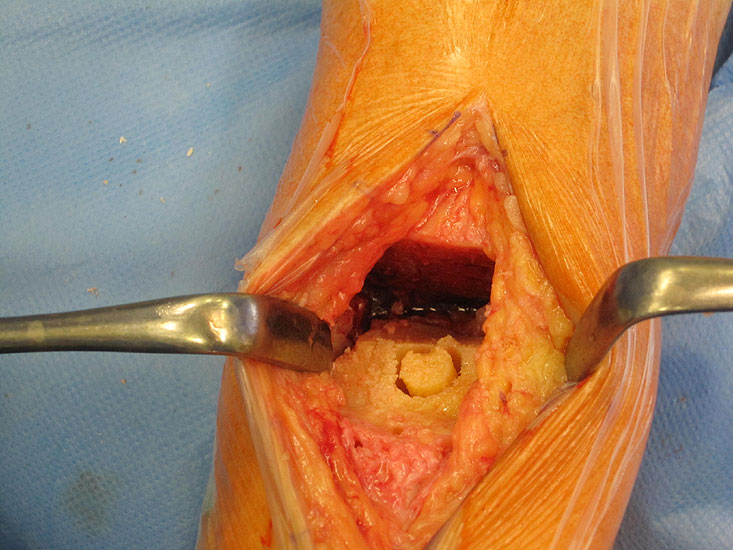

• Prothesenplanung anhand von Röntgenschablonen (Abb. 1 und 2).